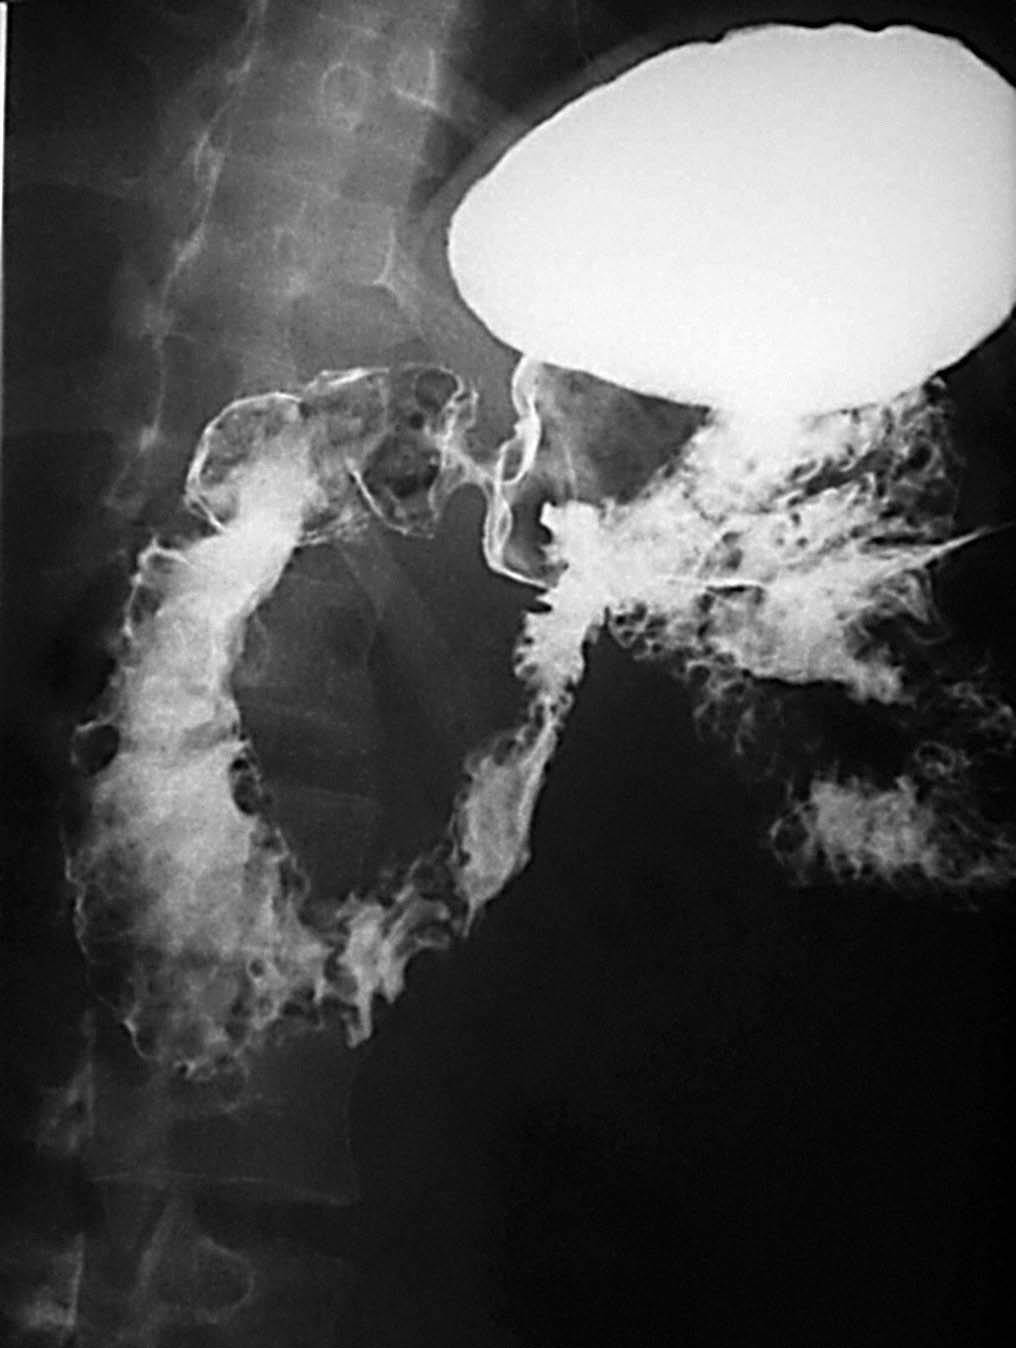

La EC se define como un proceso transmural inflamatorio crónico de etiología desconocida. De carácter recurrente, segmentario y granulomatoso, tiende a provocar complicaciones tales como abscesos y trayectos fistulosos. Se localiza en cualquier segmento del tracto digestivo, desde la boca al ano, aunque asienta de forma preferente en el íleon terminal, en íleon proximal y colon ascendente (fig. 1). Se acepta que en un 55% de los casos hay afectación del íleon terminal y del colon, en un 30% de los casos sólo de intestino delgado y que la afectación exclusiva del colon acaece en un 15%9.

Fig. 1.--Enfermedad de Crohn, afectación segmentaria del tracto digestivo con localización duodenal (A) e ileal (B) en el mismo paciente.